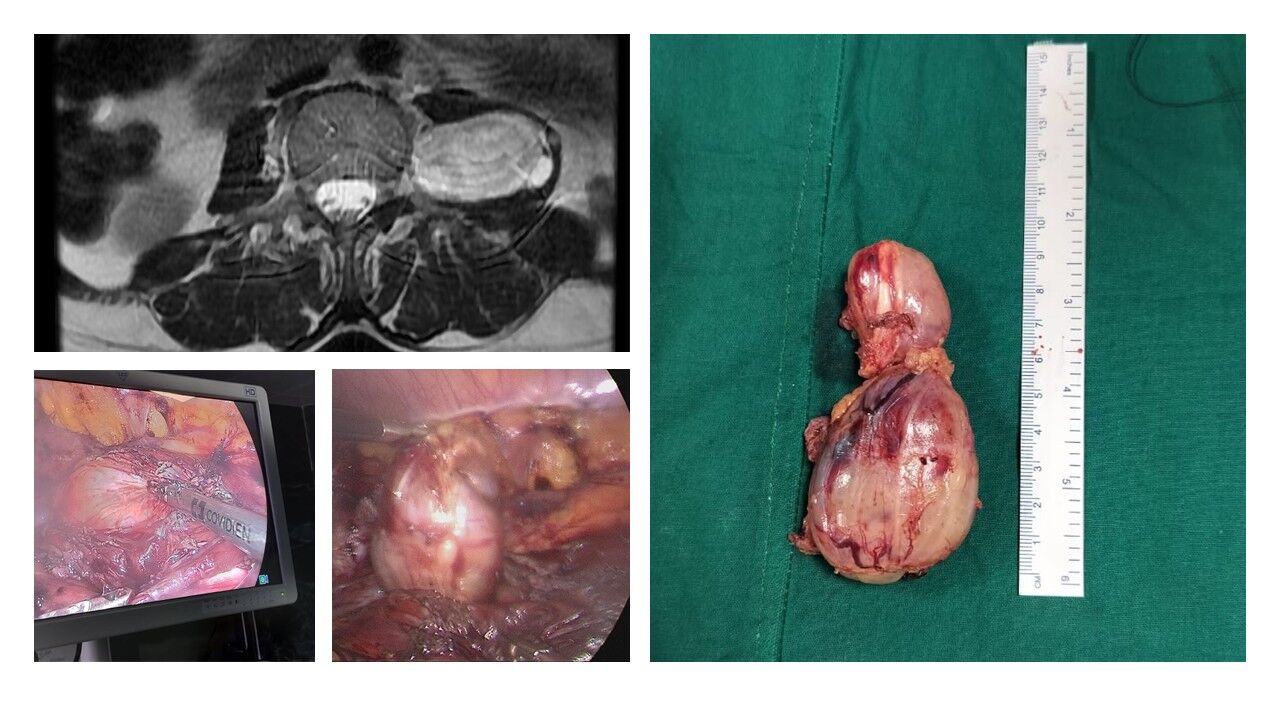

A 50-year-old woman presented with a left lumbar paraspinal schwannoma, a benign nerve sheath tumor located deep in the retroperitoneal space. MRI revealed two well-defined lesions measuring 10 × 5 cm, extending from L2 to L5, with no intracanalicular extension. She successfully underwent excision of the tumor through a transperitoneal minimally invasive approach, which provided excellent visualization, precise dissection, and safe tumor removal.

Although retroperitoneal masses are often considered a relative contraindication for laparoscopic surgery, in this case the patient underwent safe paraspinal mass removal with no intraoperative complications, minimal blood loss, and faster recovery compared to conventional open surgery.

The postoperative course was uneventful; the patient recovered smoothly and was discharged on the 4th postoperative day without neurological deficits or perioperative complications.